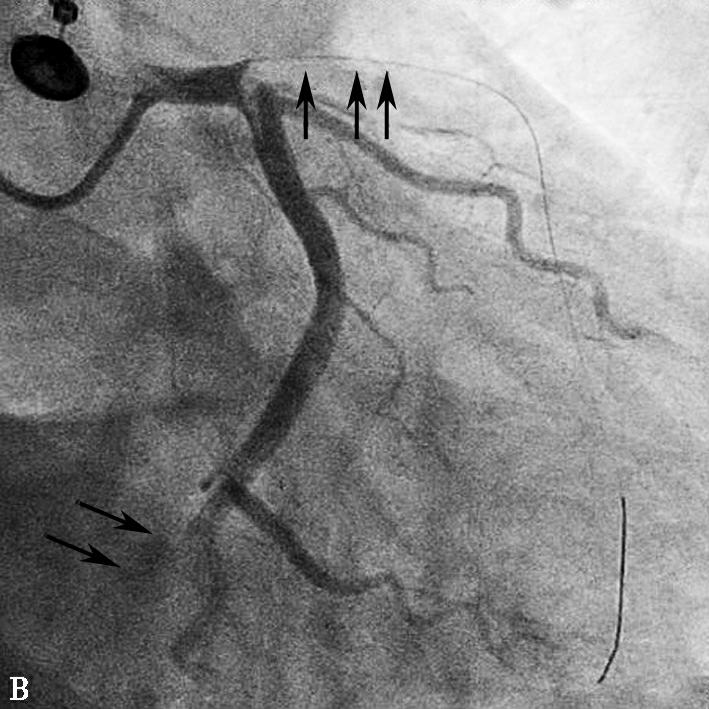

图1当地心电图及急诊PCI结果

A.当地市医院急诊心电图提示:Ⅱ、Ⅲ、aVF、V2~V5导联ST段弓背向上抬高;B.急诊造影提示:LAD开口闭塞,回旋支远段栓塞;C.PCI术后,LAD TIMI 2级,LCX远段血流未恢复